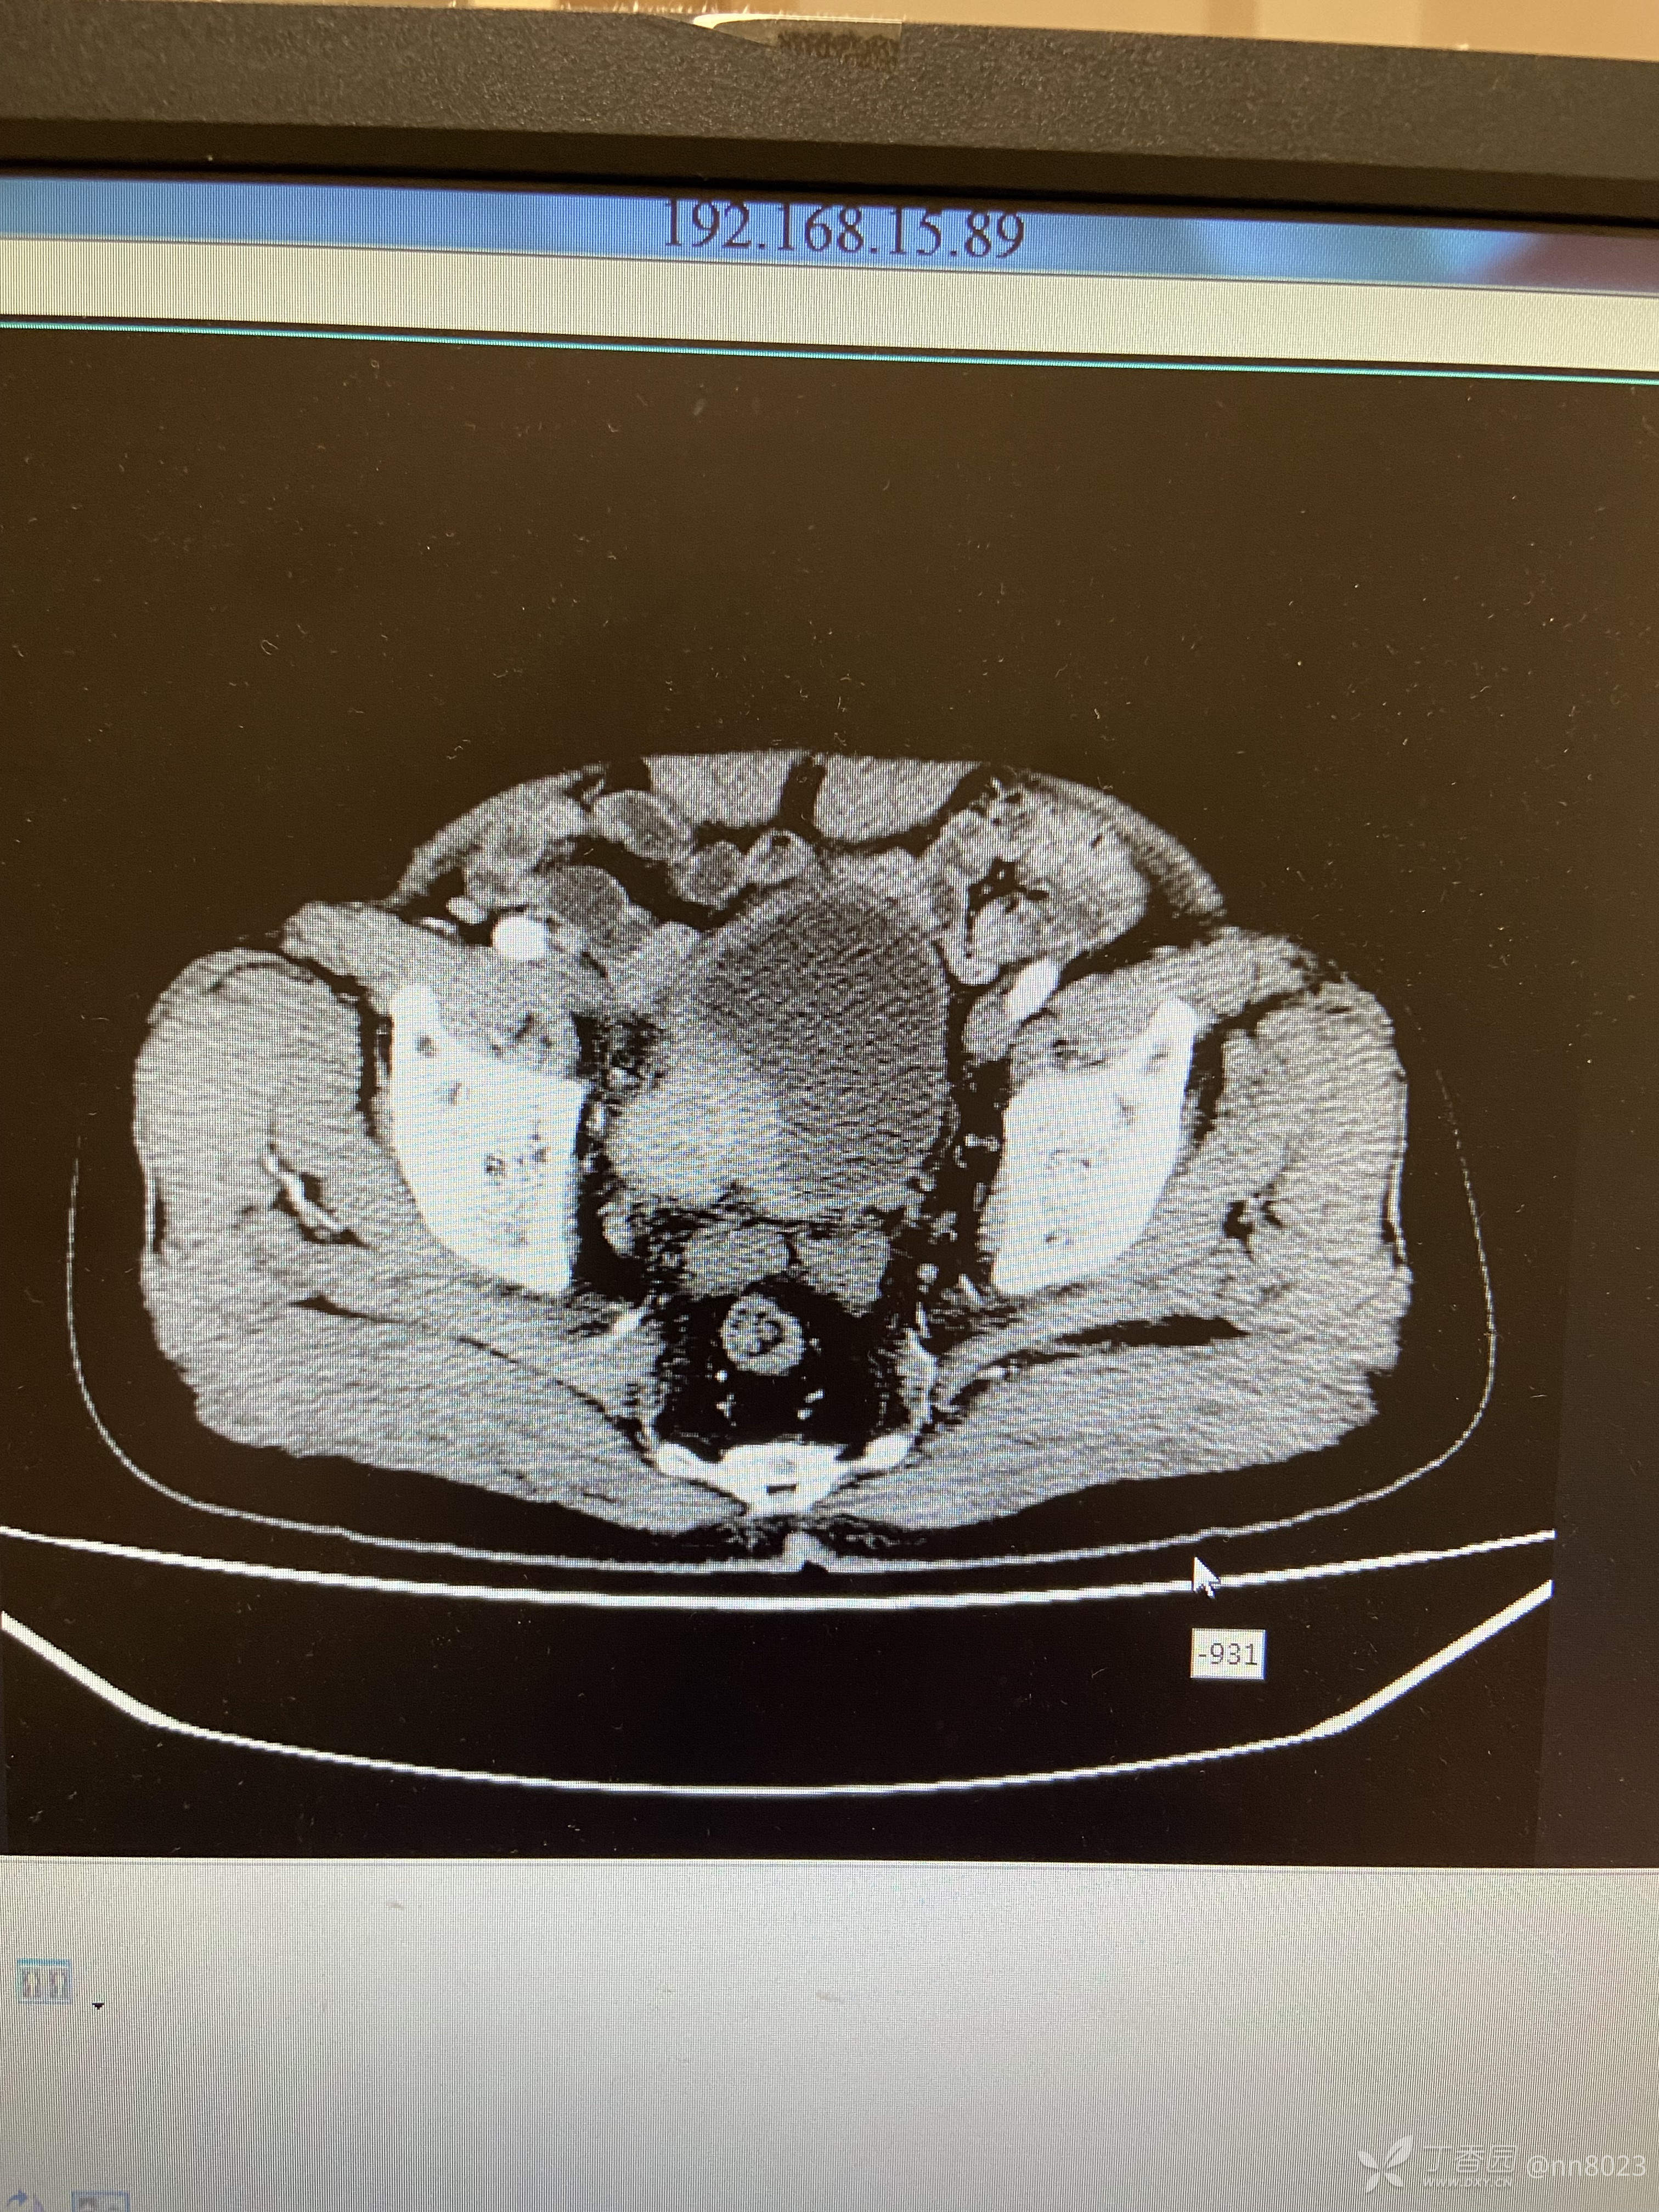

xiaospring +3 丁当66岁男性患者,因尿频尿痛于当地医院检查,彩超提示膀胱占位,完善增强CT